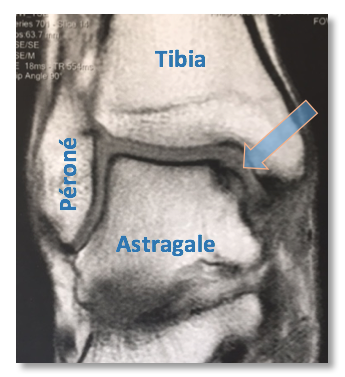

Il s’agit généralement d’une lésion du cartilage de l’astragale se produisant lors du déplacement en varus du pied, sur l’angle astragalien externe, côté malléole externe (Images 5 et 6).

Image 6 : LODA externe sur une coupe IRM.